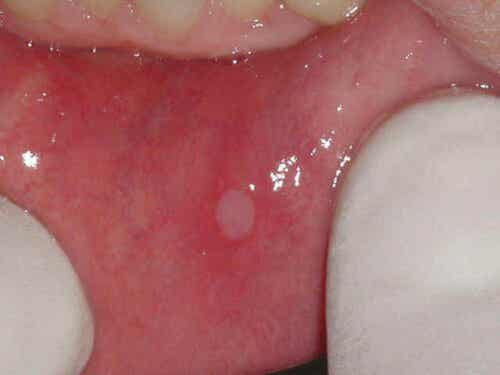

Deze laesies bestaan meestal uit een enkele ronde, witachtige laesie omgeven door een ontstoken gebied. Ze zijn zelden groter dan 8 millimeter. Er is bovendien vaak meer dan één zweer en deze zijn meestal kleiner dan 3 millimeter. Er zijn ook gevallen waarin deze laesies groter zijn en genezing complexer is.